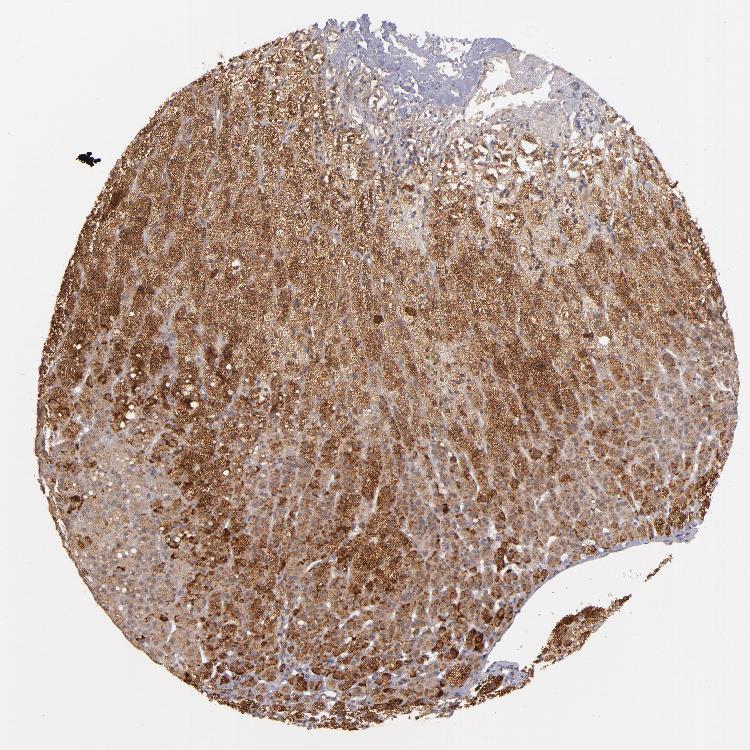

ADRENAL GLAND - Antibody stainingi

Antibody staining in the annotated cell types in the current human tissue is reported as not detected, low, medium, or high, based on conventional immunohistochemistry profiling in selected tissues. This score is based on the combination of the staining intensity and fraction of stained cells.

Each image is clickable and will lead to virtual microscopy that enables deeper exploration of all samples and also displays staining intensity scores, fraction scores and subcellular localization as well as patient and tissue information for each sample.

Antibody HPA002898

Glandular cells Medium